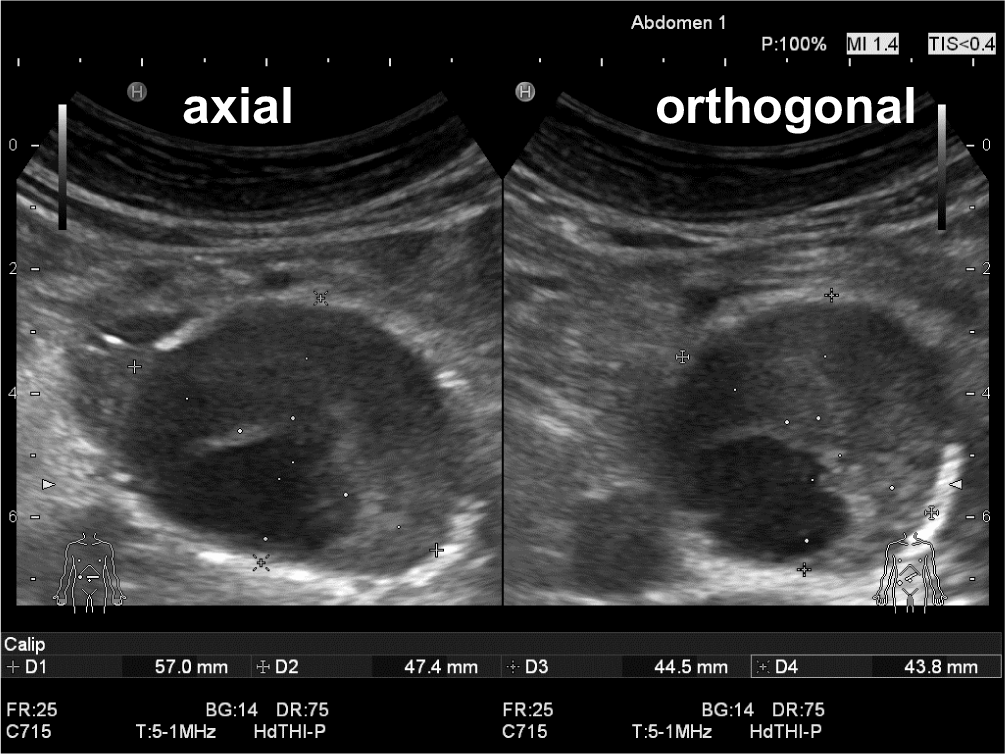

Millimeter entscheiden über die Operationsindikation

Dies zeigt, wie Millimeter (neben Begleiterkrankungen, Operabilität, Operationsmethode, Aneurysmakonfiguration und nicht zuletzt Patientenwille) über eine Operationsindikation entscheiden und wie wichtig die exakte Bestimmung des reellen AAA-Durchmessers ist. Selbst bei gradlinigen Aortenverläufen ohne wesentliche Elongation kann schon der schräge Verlauf vom Zwerchfelldurchtritt bis zu Bifurkation (von dorsal nach ventral) durch die Lendenlordose insbesondere bei schlanken Personen axial v. a. in der a.-p.-Ebene zu Überschätzungen von bis zu 1 cm führen (Abb. 7; Videoclip 4).

Abb. 7

Die durch die Lendenlordose in ihrem Verlauf vom Zwerchfelldurchtritt zur Aortenbifurkation nach ventral verlagerte Aorta führt auch ohne wesentliche Aortenelongation zur Gefahr der Überschätzung des Aneurysmadurchmessers in der anterior-posterioren Messebene. Im Längsschnitt ist der Verlauf beurteilbar, und der Aortendurchmesser muss von axial 50 mm (D3) auf orthogonal reelle 41 mm (D1) korrigiert werden (vgl. Videoclip 4). Neben der Überschätzung des abdominalen Aortenaneurysmas (AAA) kann in axialer Messebene allein durch geringes kraniokaudales Kippen des Transducers auf der Haut eine erhebliche Inter- und Intraobservervariabilität entstehen